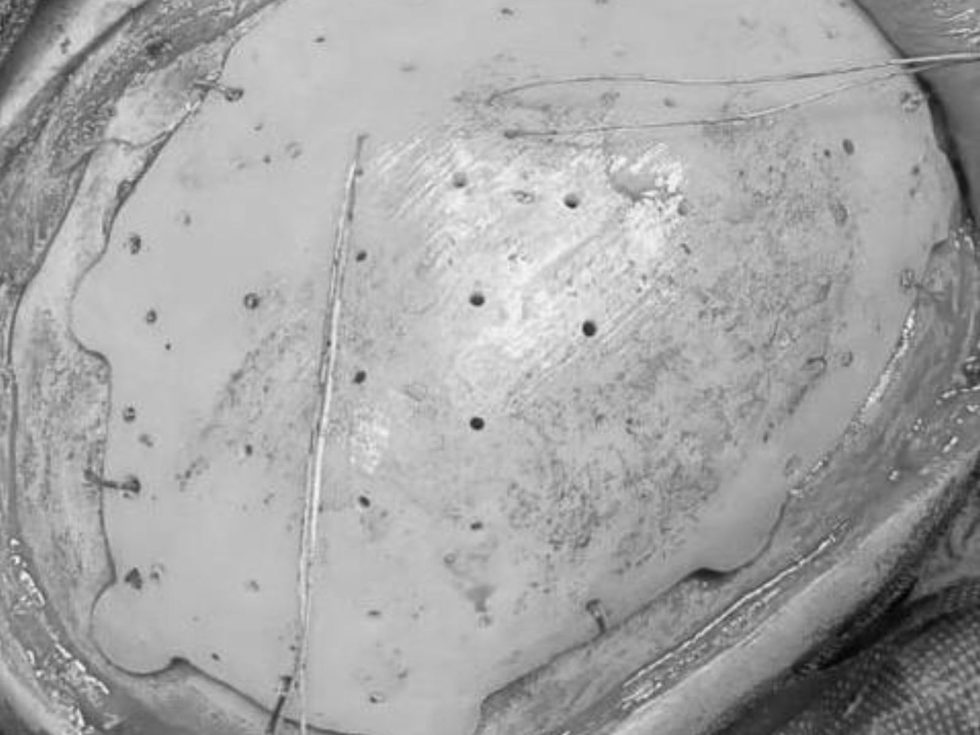

Сложный послеоперационный дефект черепа в левой лобно-теменно-височной области доставлял пациенту косметический дискомфорт. Врачи Оренбургского центра хирургии и травматологии решили провести плановую операцию по восстановлению целостности черепа.

Чтобы закрыть дефект костей, для юноши заказали и выполнили индивидуальный имплант. Его изготовили по снимкам компьютерной томографии в 3-D режиме.

фото: Оренбургский центр хирургии и травматологии